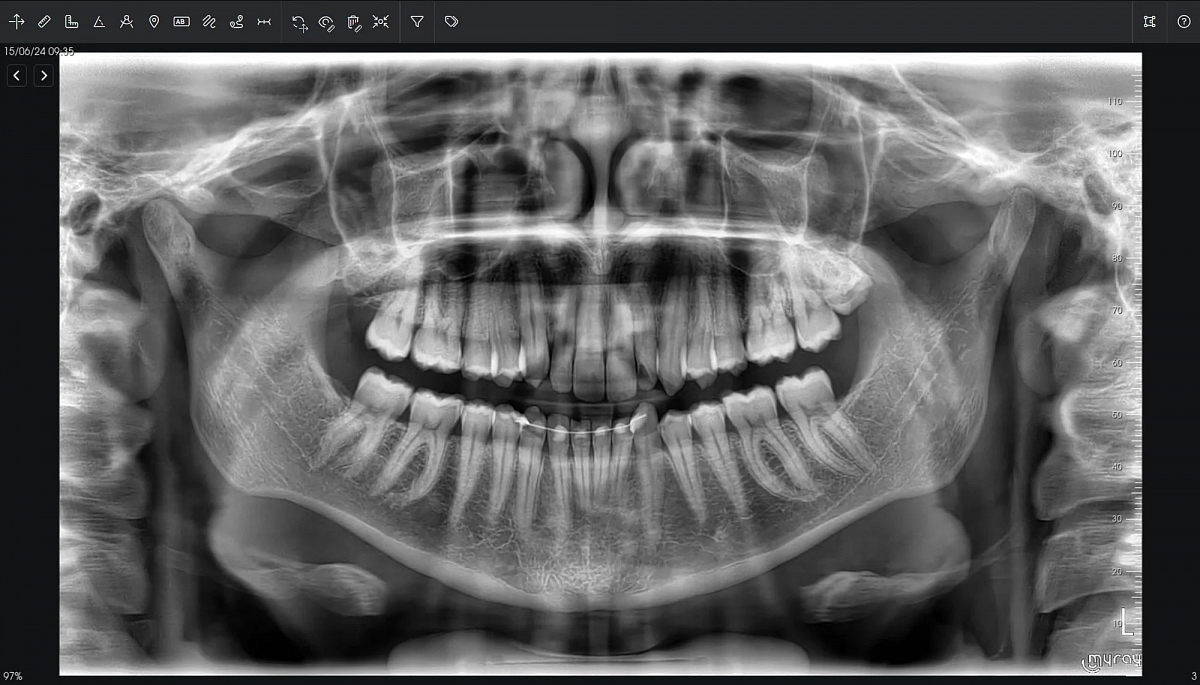

Diagnostinės galimybės

2D vaizdai

- Panoraminiai (PAN) vaizdai su keliais fokusavimo sluoksniais

- Detalios žandikaulių sričių projekcijos

3D CBCT vaizdai

- SuperHD CBCT su MultiFOV funkcija nuo mažiausio (4x4) iki didžiausio (15x16) lauko

- Greitas 360° skenavimas ir mažos dozės protokolai

- Tiksli kaulinės struktūros diagnostika implantologijai, chirurgijai, ortodontijai ir ENT analizėms